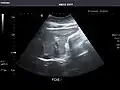

Renal ultrasonography

Ultrasound scan of a kidney (right side)

Ultrasonography of the kidneys is essential in the diagnosis and management of kidney-related diseases. The kidneys are easily examined, and most pathological changes in the kidneys are distinguishable with ultrasound.[7]